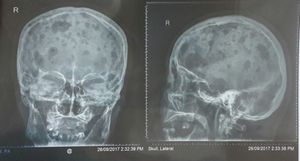

What do you think about this this skull xray????

Multiple myeloma, defined as punchout lesions on the bones, in this picture the skull.

multipule osteolytic bone metastasis most probably multipule myloma?